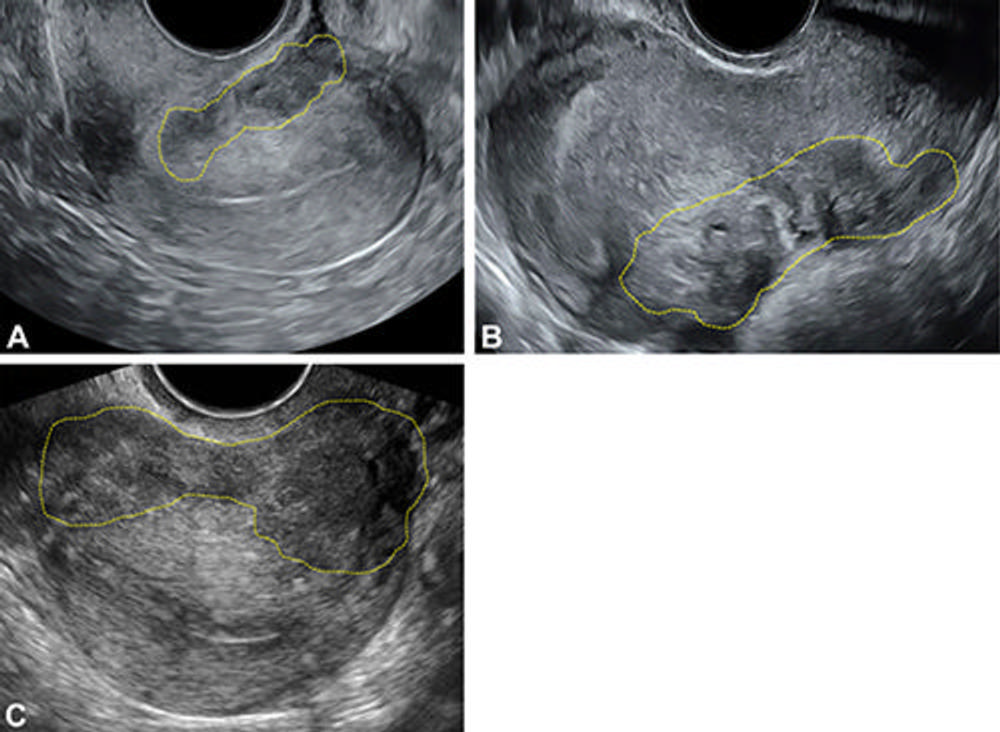

Figure 8. (A–C) Transvaginal US images in three reproductive- age individuals (a 34-year-old, 41-year-old, and 37-yearold patient), all presenting with chronic pelvic pain, demonstrate deep endometriosis of the outer uterine serosa (yellow outline) in retroflexed uteri, which is a category A (direct endometriosis) observation. Images were obtained with the (A) transducer in the posterior fornix in longitudinal view, (B) transducer in the anterior fornix in longitudinal view, and (C) transducer in the posterior fornix in transverse view.